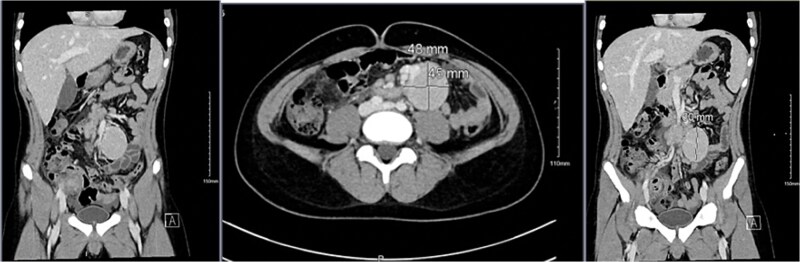

Castleman病是一种罕见的淋巴细胞增生性疾病,病因不明,其最常见的症状是纵隔淋巴结肿物。虽然它在年轻人中很少见,但在成年人中很普遍。我们报告一个病例14岁的男孩谁是入院的外科急性右侧腹痛,怀疑急性阑尾炎。术前腹部影像学检查显示炎性阑尾及大肠系膜肿块。经组织病理学检查证实为急性阑尾炎及单中心肠系膜肿块,经腹腔镜手术切除。

The most prevalent symptom of Castleman disease, a rare lymphoproliferative condition with an unclear etiology, is a mediastinal nodal mass. While it is quite uncommon in youngsters, it is prevalent in adults. We report a case of a 14-year-old boy who was admitted to the department of surgery for acute right-sided abdominal pain, with suspected acute appendicitis. Preoperative imaging investigation of the abdomen showed an inflammatory appendix as well a large mesenteric mass. Histopathology examination confirmed the diagnosis of acute appendicitis and mesenteric mass unicentric Castleman after resection by laparoscopic approach.